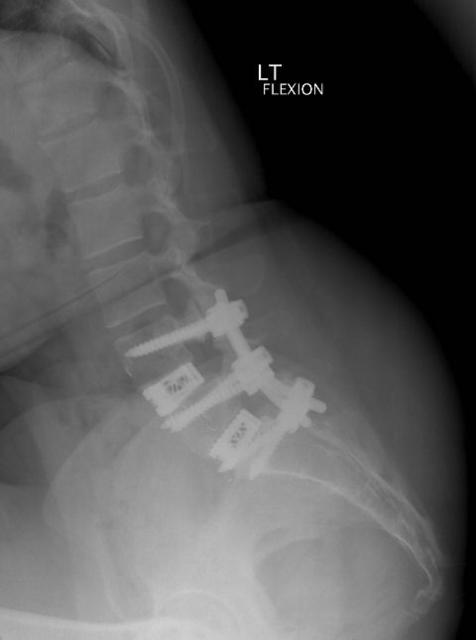

2011-02-17-01.jpg Date: 02/22/11

2011-02-17-02.jpg Date: 02/22/11